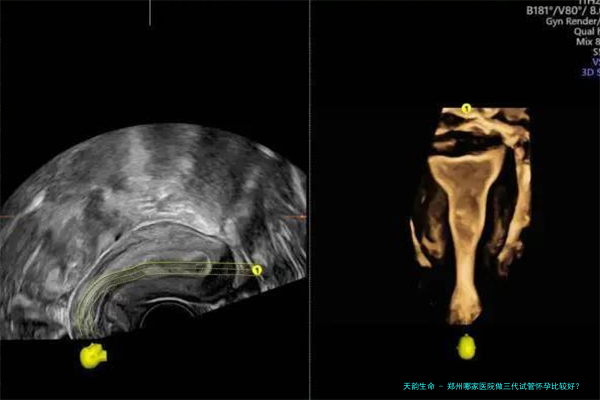

郑州大学第一附属医院辅助生殖医学中心是河南省较早开展人类辅助生殖技术的医疗机构之一,拥有坚实的医学资质力量和先进的医疗设备。该中心开展囊括试管受孕-胚胎移植(试管婴儿(IVF)-ET)、卵胞浆内单精子显微注射(显微受精技术)和移植前遗传学诊断/检查筛选(PGD/PGS)等全方位的辅助生育技术。据统计,该院三代试管婴儿的临床怀孕率可达60%左右,在河南省内处于顶尖水平。费用方面,1个周期的三代试管费用大约在5-8万元元钱,具体费用会根据病患的身体情况和用方子案有所差异。

郑州大学第三附属医院(河南省妇幼保健院)生殖医学中心是河南省关键的妇幼保健机构,在生殖医学范围具有较高的声誉。该中心拥有先进的实践室器械和专业的医疗集体,开展囊括三代试管婴儿在内的多项辅助生殖技术。该院看重个体化治疗方案的制定,根据患者的详尽情形制定合适的诊疗方案,以提高试管婴儿的成功率。据认识,该院三代试管婴儿的成功率也在50%以上。费用方向,1个周期的费用大概在四万到六万元左右,详细依据于于患者的用药情况和治疗方案。